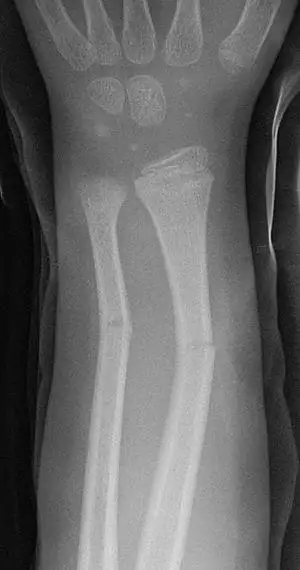

Greenstick fractures on X-ray.

A greenstick fracture is a fracture in a young, soft bone in which the bone bends and breaks. Greenstick fractures occur most often during infancy and childhood when bones are soft. The name is by analogy with green (i.e., fresh) wood which similarly breaks on the outside when bent.

The greenstick fracture pattern occurs as a result of bending forces. Activities with a high risk of falling are risk factors. Non-accidental injury more commonly causes spiral (twisting) fractures but a blow on the forearm or shin could cause a greenstick fracture. The fracture usually occurs in children and teens because their bones are flexible, unlike adults whose more brittle bones usually break.